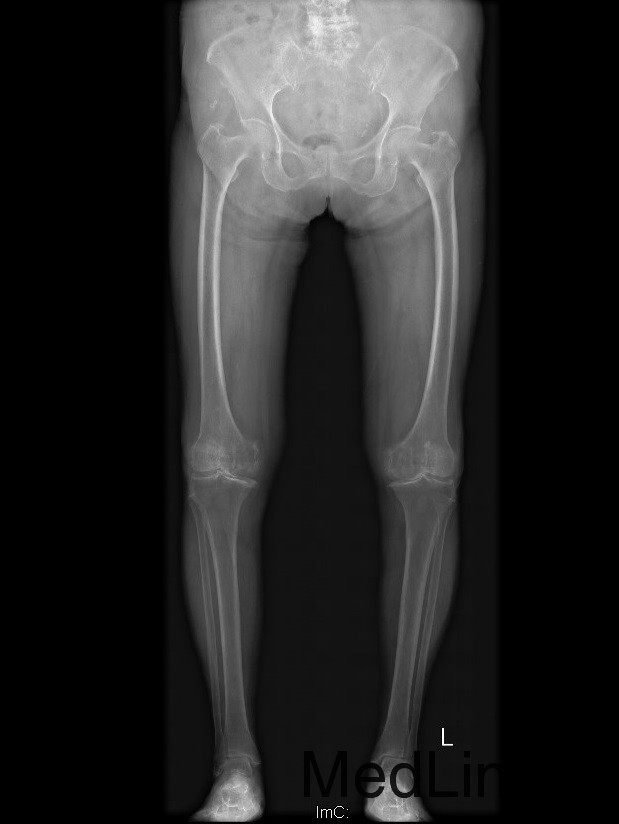

主诉:双膝疼痛20年,加重伴行走困难8年 现病史:20年前患者开始出现双膝关节疼痛,负重行走、下楼时疼痛加重,休息后可缓解,尚可下蹲。,自行购买口服止痛药,关节腔内注射玻璃酸钠、理疗等处理,疼痛时有缓解。但症状反复发作。8年前疼痛加重且行走困难,扶拐行走仅能坚持约10余米,上下楼梯艰难,下蹲不能,以左侧为重。现患者为行进一步治疗入院。

查体:查体:跛行步态,双膝关节屈曲内翻畸形,双膝内侧间隙压痛,双膝髌股关节间隙压痛,左膝伸-20°,屈110°内翻10°。右膝伸-20°,屈110°内翻10°,双膝屈伸活动时髌骨下摩擦感(+)。 辅助检查:双侧髌股关节内侧间室变窄,关节边缘骨赘增生,软骨下骨硬化。

诊断:1、双膝骨关节炎伴屈曲内翻畸形 左侧重2、高血压病(2级高危、) 治疗:在全麻下行左侧全膝关节置换术+软组织松解术,术后予以抗炎+抗凝+镇痛+补液+护胃治疗,并指导其功能锻炼。